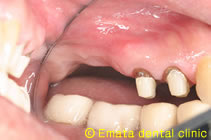

サイナスリフト治療中

このときの臨床判断は安全確実な治療を優先し、同時にインプラント埋入はせず、2ヶ月たって歯肉が治ってからインプラント埋入しました。

開窓(骨の削除)はお痛みや腫れが出ないように出来るだけ小さくします。

治療中は麻酔医による静脈鎮静法を併用しています。静脈内鎮静法とは麻酔専門の医師が手術による不安や痛みを取り除き、血圧上昇や呼吸不全をふせぐ全身管理を行なう目的と、静脈から痛み止めや腫れ止めを処方でき、手術が安全かつスムーズに行なうことが可能です。手術中は、全身麻酔とは違い、意識はありますが半分眠ったような状態になりますので、緊張がほぐれて、だいぶ楽に手術を受けていただけると思います。